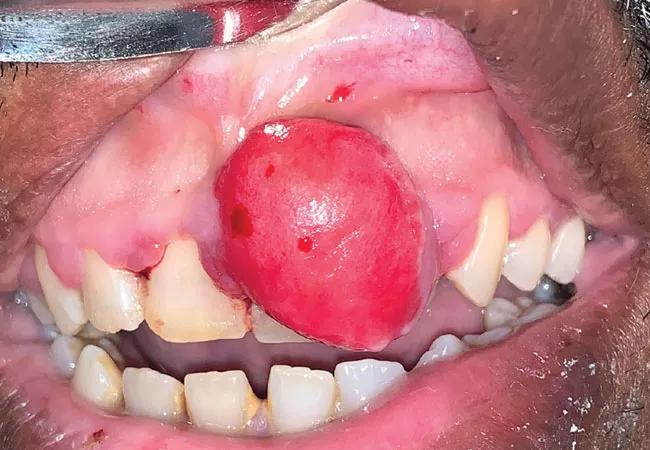

On physical examination, a large, firm, non-tender, sessile mass was visible on the gingiva of the upper incisors (see above). The surface was erythematous and smooth with no ulceration. Excisional biopsy of the entire mass was performed under local anesthesia. Histopathology revealed a fibroma with fibrous strand proliferation and no dysplastic changes, suggesting a diagnosis of benign fibroma. No additional treatment was necessary.

The differential diagnosis of a gingival mass includes peripheral ossifying fibroma, peripheral giant cell granuloma and pyogenic granuloma.1 Fibromas are benign growths that occur most commonly along the buccal mucosa secondary to accidental biting of the cheek.2 Due to their slow growth, they typically have a subacute onset.

The gingival fibroma in our patient stemmed from poor oral hygiene resulting in plaque with a calculus deposit acting as an irritant. This is histologically different from a cutaneous fibrous neoplasm, which is rarely seen in the mucosal tissue in the head and neck.3 Excisional biopsy is diagnostic and curative. Laser removal has been described in the literature.4 Recurrence is prevented with attention to good oral hygiene.5